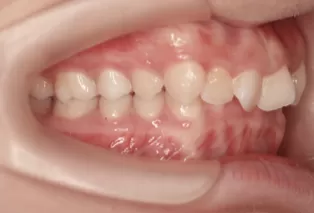

Photos intra-orales